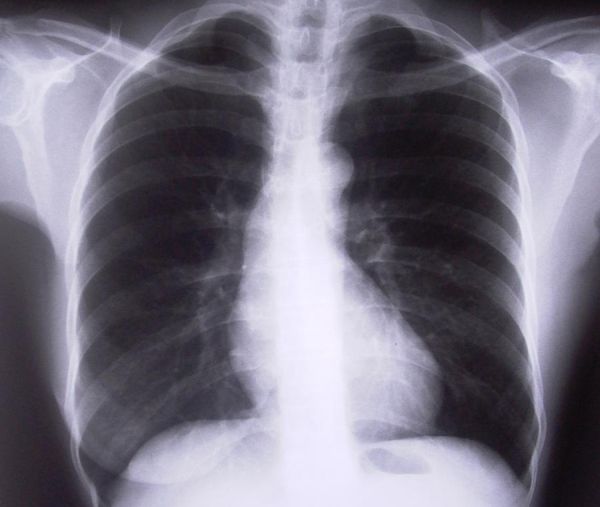

Dijagnoza se temelji na nalazu ventilacijsko/perfuzijske scintigrafije, CT angiograma i plućne angiografije. Dijagnoza se često dosta sporo postavlja jer su simptomi i znakovi plućne embolije nespecifični. Naime, plućna embolija ima slične simptome kao ishemija srca, popuštanje srca, egzacerbacija KOPBa, pneumotoraks, pneumonija, sepsa, akutni plućni sindrom i akutna uznemirenost s hiperventilacijom. Obrada započinje pulsnom oksimetrijom, EKG–om i RTG–om pluća.